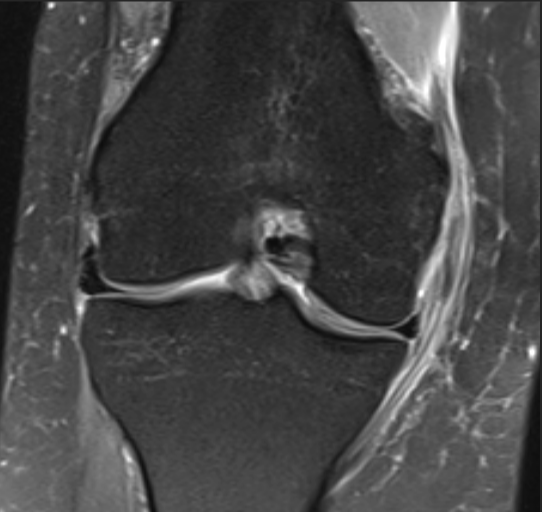

Grade 2 MCL injury